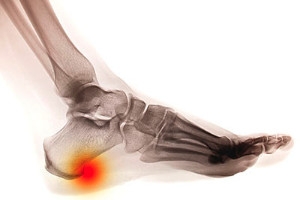

Heel spurs are essentially bone-like growths that occur when calcium collects between your heel and arch. There can be many causes for heel spurs that include arthritis and poor footwear. While they can cause pain, they are almost impossible to detect without the help of a doctor. Since the pain caused by heel spurs is similar to that of other foot injuries, specialists may need to perform a variety of tests or X-rays. Rest, cold compressions, and shoe inserts are some common treatments for heel spurs.  However, it is important to consult with a podiatrist in case further treatments, such as injections, prescriptions, or surgery, are necessary.

Heel spurs are formed by calcium deposits on the back of the foot where the heel is. This can also be caused by small fragments of bone breaking off one section of the foot, attaching onto the back of the foot. Heel spurs can also be bone growth on the back of the foot and may grow in the direction of the arch of the foot.

Older individuals usually suffer from heel spurs and pain sometimes intensifies with age. One of the main condition's spurs are related to is plantar fasciitis.

The pain associated with spurs is often because of weight placed on the feet. When someone is walking, their entire weight is concentrated on the feet. Bone spurs then have the tendency to affect other bones and tissues around the foot. As the pain continues, the feet will become tender and sensitive over time.

There are many ways to treat heel spurs. If one is suffering from heel spurs in conjunction with pain, there are several methods for healing. Medication, surgery, and herbal care are some options.